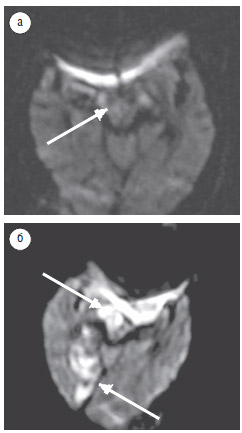

Результаты нашего исследования свидетельствуют, что в период до 24 ч после начала инсульта инфарктный очаг не выявлен у 33% пациентов, а чувствительность ДВИ в выявлении острого инфаркта ствола головного мозга на протяжении этого времени составила 67%. По данным С. Oppenheim и соавторов (2000), в течение 24 ч от проявления клинических симптомов ложноотрицательные результаты выявляли у 34% обследованных с инфарктом ствола головного мозга. H. Toi и соавторы (2003) на ДВИ, полученных в течение 2 ч после клинических проявлений инфаркта, не выявили очагов поражения у 2 (11%) пациентов из 18, но обнаружили инфарктную зону при повторных исследованиях через 19 и 24 ч соответственно. В нашем исследовании у 1 пациента, обследованного 2 раза в течение 24 ч после развития инфаркта (через 12 ч и 23 ч соответственно), на первом ДВИ достоверных признаков ишемии не выявлено (рис. 3а), но на повторном ДВИ обнаружены ишемические очаги в правой ножке и правой затылочной доле мозга (рис. 3б).

Рис. 3. Пациент М., 87 лет: а — ДВИ (аксиальная проекция), срез на уровне ножек мозга, через 12 ч после развития заболевания; в правой ножке

мозга — незначительное повышение МР-сигнала, предположительно — очаг ишемии; б — ДВИ (аксиальная проекция), срез на уровне ножек

мозга, через 23 ч после развития заболевания; в правой ножке мозга и в правой затылочной области определяются гиперинтенсивные очаги,

соответствующие острому инфаркту